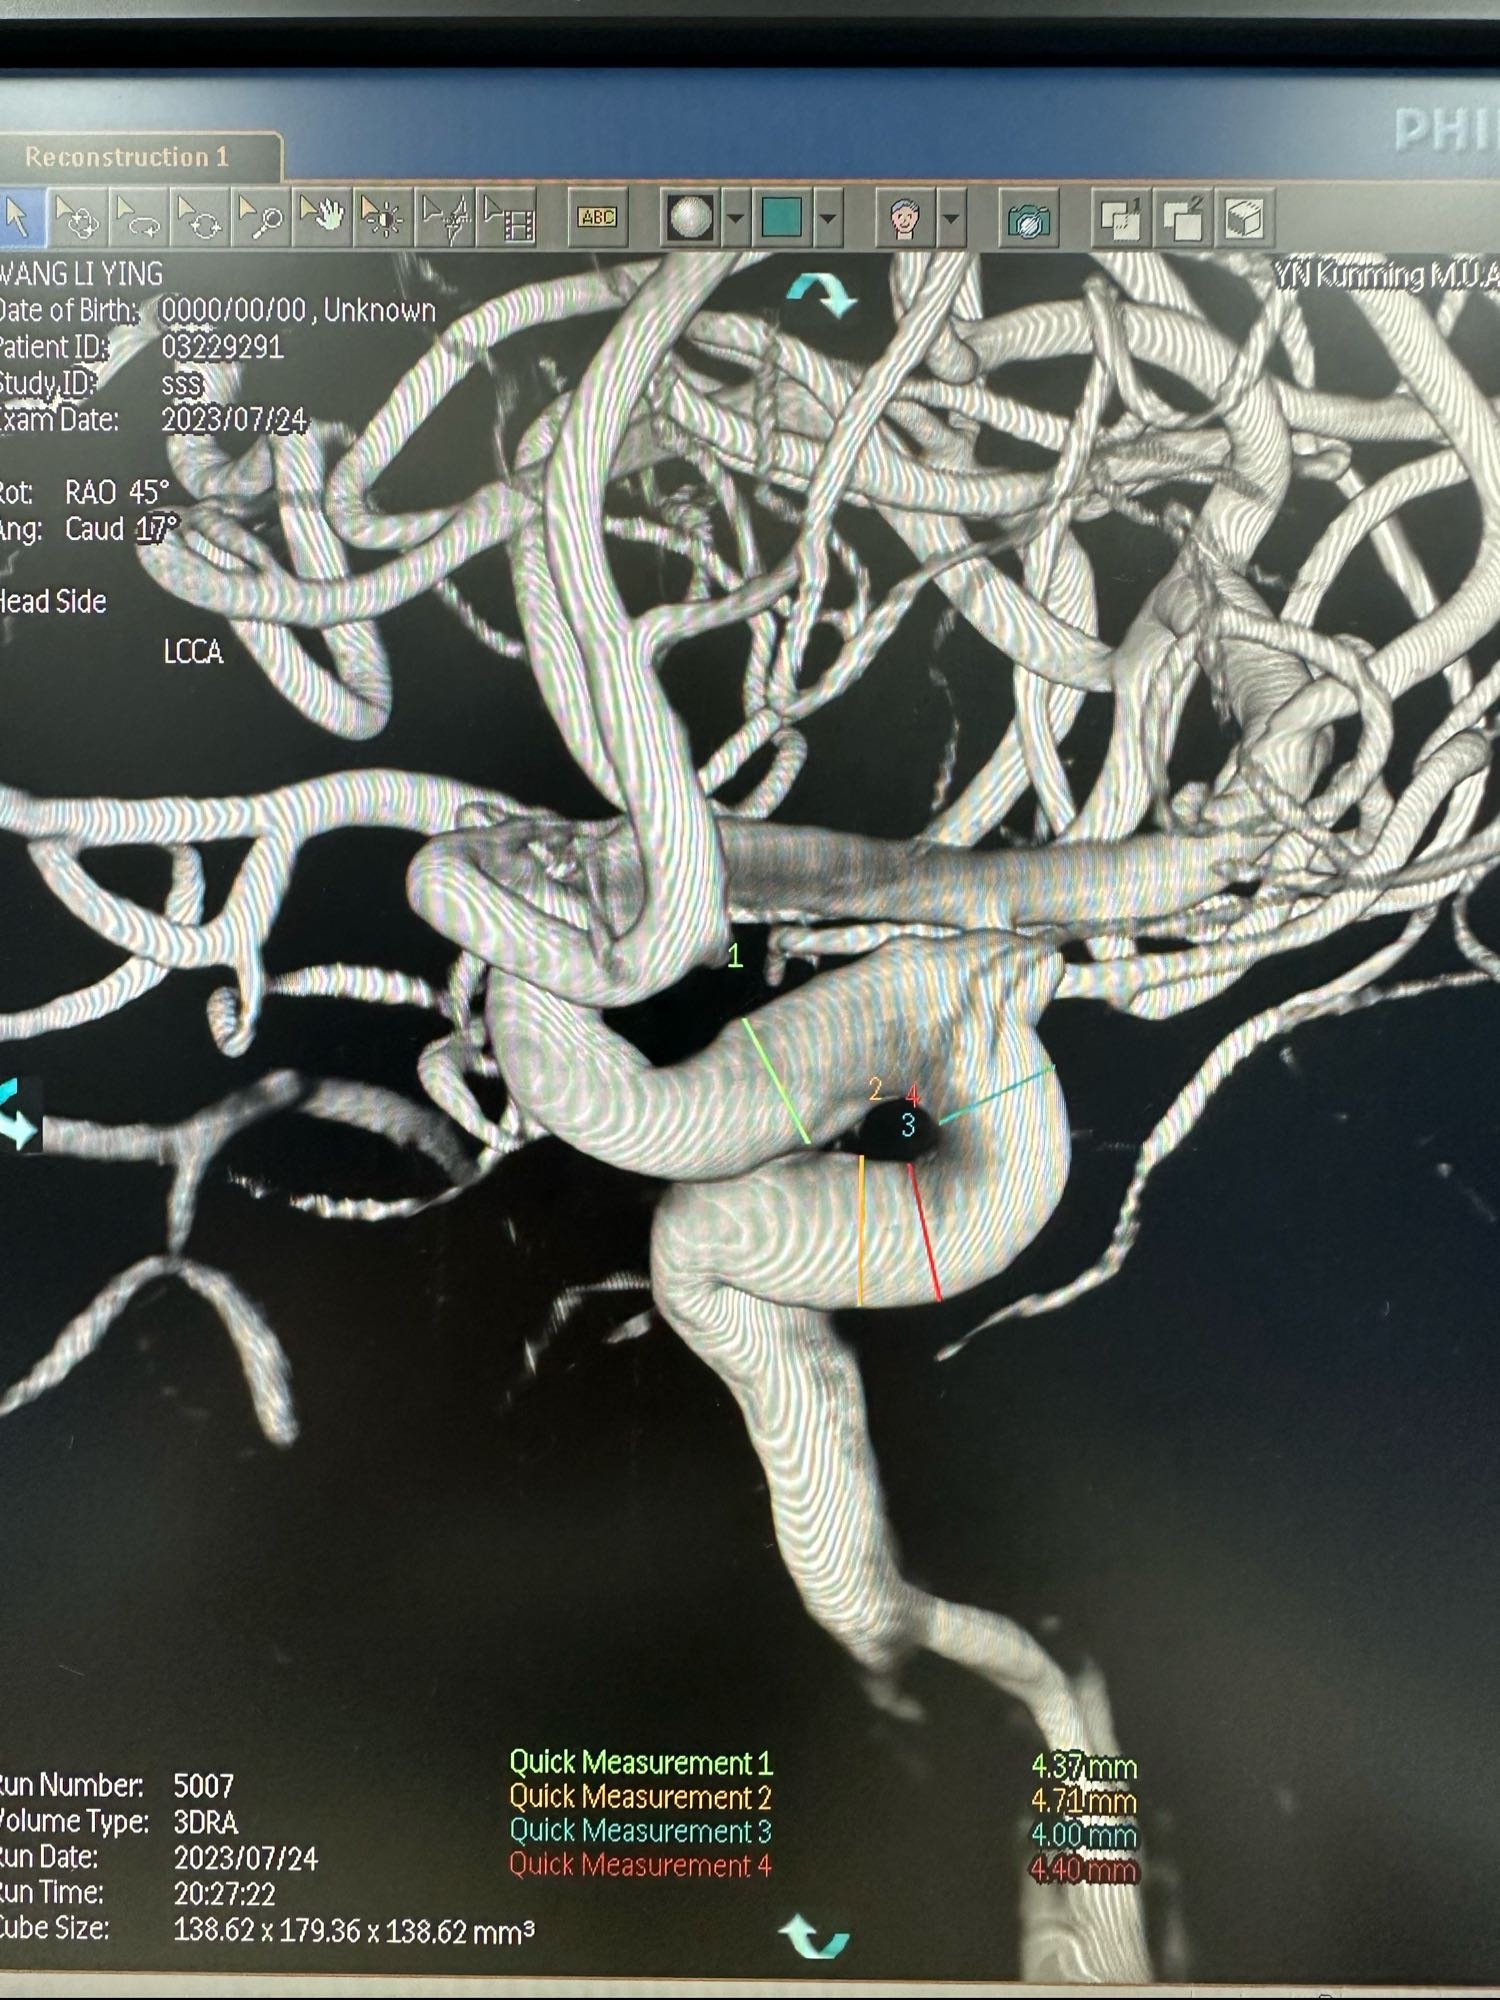

术前的3D

王LY,女,71岁,左侧眼动脉段动脉瘤,给予Lattice密网支架植入